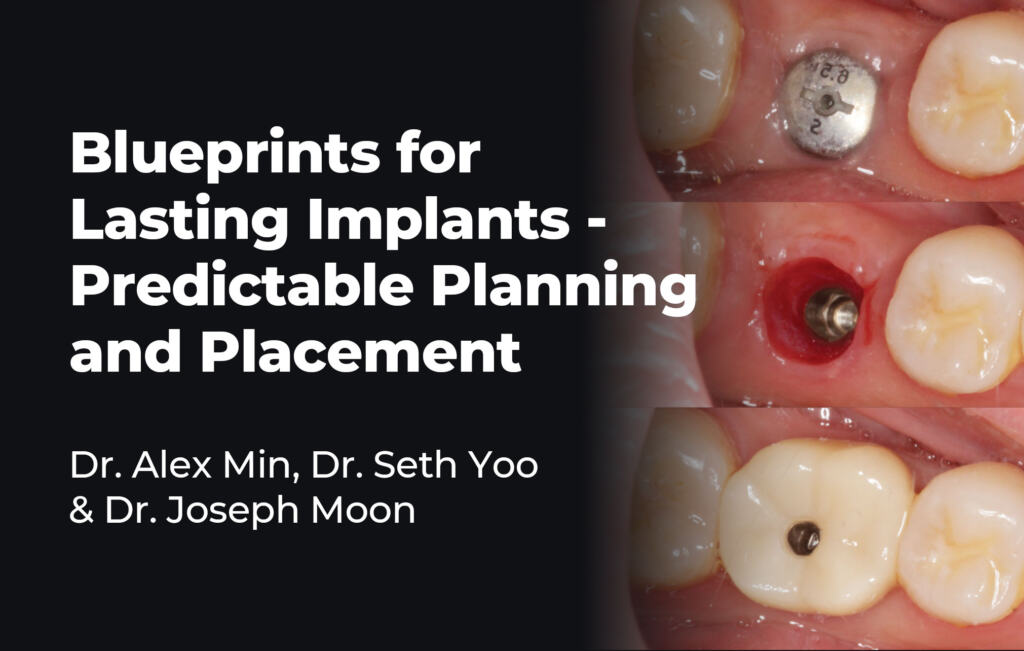

Course Director

Dr. Alex Min

Dr. Alex (Jung Hong) Min is an associate dentist at Dental Boutique Geelong. He graduated from the Melbourne Dental School in 2014 and is currently completing a Master of Science in Oral Implantology at Goethe University in Frankfurt, Germany. Committed to staying at the forefront of dental implantology, Dr. Min actively pursues the latest advancements in the field.

Over the course of his career, he has delivered implant treatments across various clinics in Melbourne and now focuses on more complex cases, including full-mouth rehabilitations. He also provides mentorship to numerous dentists with whom he currently works or has collaborated in the past.

Dr. Min is trained in phlebotomy, enabling him to extract blood and isolate growth factors and stem cells to support enhanced healing following implant surgery. He is deeply dedicated to improving the oral health and comfort of patients with severely compromised dentition. Known for his caring and thorough approach, Dr. Min places a strong emphasis on patient education, ensuring his patients clearly understand their diagnoses and treatment options.

Dr. Seth Yoo

Dr. Seth Yoo takes the time to listen to his patients to tailor treatment plans suited to their individual needs. He is committed to ongoing development and regularly updates his knowledge of current techniques. His areas of interest include implant dentistry, All-on-X treatments, and surgical procedures focused on restoring oral function and aesthetics.

He completed the Master Implant Program (Bii) under prosthodontist and clinical associate professor Dan Brener, as well as Advanced Bone Grafting with Cadaver Hands-On Training (CII). He also attended the Dental Implantology Advanced Course Live Surgery (GIIA) in Tijuana, Mexico, working with a team of specialists including a periodontist and an oral maxillofacial surgeon.

Additionally, Dr. Yoo completed the All-on-Implants™ Treatment Concept Mini-Residency with oral maxillofacial surgeon Dr. Han Choi and prosthodontist Dr. Alan Payne. He is a member of DSD (Digital Smile Design), having completed the DSD Residency to further develop his comprehensive treatment planning skills.

Dr. Joseph Moon

Dr. Joseph Moon was born in South Korea and grew up in the UK and Cambodia. He has lived in Australia for the last 15 years; after falling in love with Warrnambool during a trip around Southwest Victoria in 2017, he decided to relocate there in 2018.

Joseph graduated from the University of Melbourne with Honours in 2013. Since then, he has been relentlessly committed to further education, culminating in his being awarded a Fellowship with the Royal Australasian College of Dental Surgeons (FRACDS) in 2021 – one of the highest honors for general dentists in Australia.

While Joseph is proficient in all aspects of dentistry, he is especially passionate about Implant dentistry and Invisalign treatments. He holds the prestigious status of Master Clinician in Implant Dentistry from the gIDE Institute in the USA.

Course Director

Dr. Alex Min

Dr. Alex (Jung Hong) Min is an associate dentist at Dental Boutique Geelong. He graduated from the Melbourne Dental School in 2014 and is currently completing a Master of Science in Oral Implantology at Goethe University in Frankfurt, Germany. Committed to staying at the forefront of dental implantology, Dr. Min actively pursues the latest advancements in the field.

Over the course of his career, he has delivered implant treatments across various clinics in Melbourne and now focuses on more complex cases, including full-mouth rehabilitations. He also provides mentorship to numerous dentists with whom he currently works or has collaborated in the past.

Dr. Min is trained in phlebotomy, enabling him to extract blood and isolate growth factors and stem cells to support enhanced healing following implant surgery. He is deeply dedicated to improving the oral health and comfort of patients with severely compromised dentition. Known for his caring and thorough approach, Dr. Min places a strong emphasis on patient education, ensuring his patients clearly understand their diagnoses and treatment options.

Dr. Seth Yoo

Dr. Seth Yoo takes the time to listen to his patients to tailor treatment plans suited to their individual needs. He is committed to ongoing development and regularly updates his knowledge of current techniques. His areas of interest include implant dentistry, All-on-X treatments, and surgical procedures focused on restoring oral function and aesthetics.

He completed the Master Implant Program (Bii) under prosthodontist and clinical associate professor Dan Brener, as well as Advanced Bone Grafting with Cadaver Hands-On Training (CII). He also attended the Dental Implantology Advanced Course Live Surgery (GIIA) in Tijuana, Mexico, working with a team of specialists, including a periodontist and an oral maxillofacial surgeon.

Additionally, Dr. Yoo completed the All-on-Implants™ Treatment Concept Mini-Residency with oral maxillofacial surgeon Dr. Han Choi and prosthodontist Dr. Alan Payne. He is a member of DSD (Digital Smile Design), having completed the DSD Residency to further develop his comprehensive treatment planning skills.

Dr. Joseph Moon

Dr. Joseph Moon was born in South Korea and grew up in the UK and Cambodia. He has lived in Australia for the last 15 years; after falling in love with Warrnambool during a trip around Southwest Victoria in 2017, he decided to relocate there in 2018.

Joseph graduated from the University of Melbourne with Honours in 2013. Since then, he has been relentlessly committed to further education, culminating in his being awarded a Fellowship with the Royal Australasian College of Dental Surgeons (FRACDS) in 2021 – one of the highest honors for general dentists in Australia.

While Joseph is proficient in all aspects of dentistry, he is especially passionate about Implant dentistry and Invisalign treatments. He holds the prestigious status of Master Clinician in Implant Dentistry from the gIDE Institute in the USA.

Course Description

Course Content